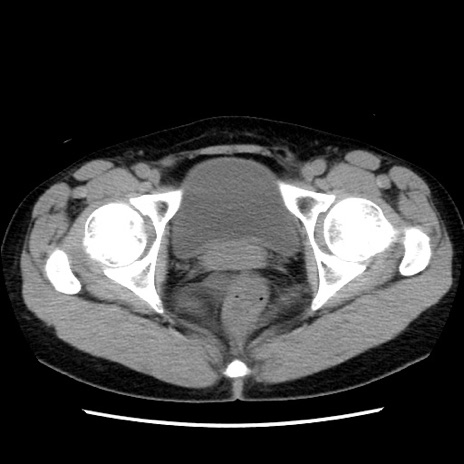

矢状断像